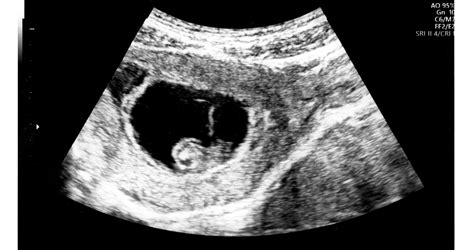

A megtermékenyülés utáni első 14 nap a sejtosztódásról és az embrió anyaméhbe történő beágyazódásáról szól. A 15. naptól kezdődik az embrió fejlődése. A szervek és szervrendszerek kialakulása a 12. hétig tart. Az ultrahangvizsgálat során a 4-5. héttől látható a petezsák, ekkor már megállapítható a terhesség, azonban az élő terhesség csak a szívműködés megjelenésével, a 6-7. héten mondható ki. Ez az időszak rendkívül szenzitív: a külső ingerek nagyobb hatással lehetnek az embrió fejlődésére, ezért fontos figyelni az életmódra (alkohol, dohányzás, gyógyszerek, fizikai megterhelés stb.), ugyanis a vetélések legnagyobb százaléka ebben az időszakban történik.

A terhességre általában a 4-6. héten, a menstruáció kimaradását követően derül ki. A várandósgondozás a terhesség megállapításával veszi kezdetét, melyet száz százalékban az ultrahangvizsgálat bizonyít. A 6-7. héten végzett ultrahangvizsgálaton általában már kimutatható a magzati szívműködés. Ez a terhesség biztos jele, de már ezt megelőzően is vannak a várandósságnak gyanú- és valószínűségi jelei.

A terhesség akkor tekinthető teljesen biztosnak, amikor az orvosi vizsgálaton az ultrahangos készülékkel történő vizsgálat alatt már látható a terhesség, és az embrió szívhangja is hallható. Ez azonban csak a terhesség 6. hetétől várható - előbb még nem biztos, hogy látszik a petezsák és nem érzékelhető a szívhang sem.